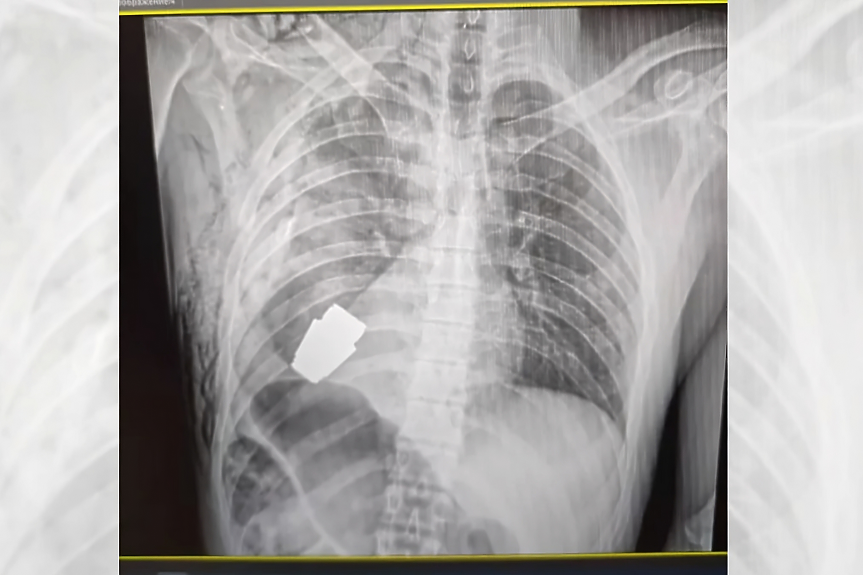

Зам.-външната министърка на Украйна Хана Маляр публикува преди дни в социалните мрежи рентгеновата снимка на пациента.

Гранатата е била под сърцето на пациента - как точно е влязла толкова дълбоко в гръдния му кош не е ясно, но по всяка вероятност става дума за стрелба с гранатомет от близко разстояние (техният обхват е цели 400 метра). Войникът е на 28 години, в момента се възстановява.

Става дума за VOG, малки, но изключително мощни фрагментационни гранати, модел за изстрелване от гранатомет. Такива се произвеждат и в България. В добавка, гранатата не е избухнала при удара във войника, но не е била инертна - а поразяващият обсег е около 6 метра. Или всички около операционната маса.